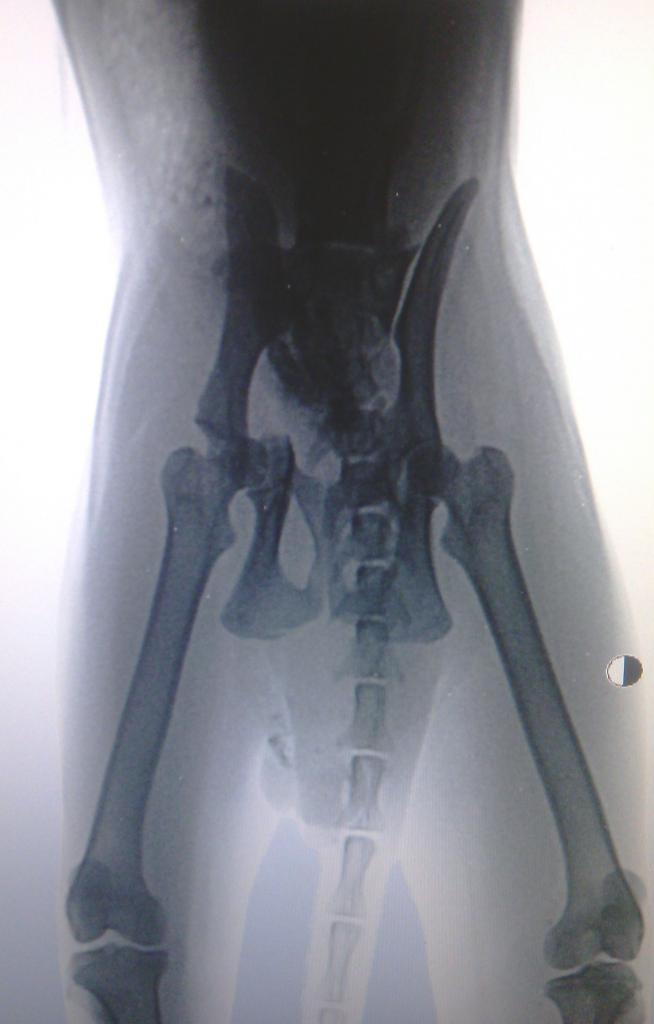

Сегодня с утра повёз его в «Хвостус». Там сделали снимки (с трудом, тоже какая-то непонятная проблема с рентгеном). Оказалось — перелом таза . Посоветовали обратиться к врачу И.Рыжему. Показал ему снимки по Вайберу — врач сказал, что нужна операция, ориентировочная стоимость 6-7 тысяч. Таких денег у меня и близко нет. Оля Black Swan подсказала, что надо с другими врачами проконсультироваться, хотя по сто гривен за консультацию я тоже много не наконсультируюсь. Главное — кот всё-таки смог сходить в туалет (были опасения, что не сможет), и с мочеиспусканием вроде бы всё нормально, как сказали в Хвостусе, хотя у нас не заметил, чтобы он мочился. Волнует вопрос: надо ли делать операцию, и что с ним будет без операции? Срастётся ли таз сам? Кот очень спокойный, в отличие от некоторых, всё время лежит на одном месте и не делает попыток куда-то рваться или исследовать квартиру. Но всё равно время от времени пытается встать. Как оно сростётся при этом?

Перелом достаточно серьезный. Дело в том, что оптимальное время за которое можно спасти тазобедренный сустав, а это где-то три-пять дней. насколько я понимаю, уже наверняка прошло больше этого интервала времени. Исходя из этого целесообразность остеосинтеза при таком застарелом переломе отсутствует. В дальнейшем для восстановления опороспособности и устранения болевого синдрома можно будет выполнить резекционную артропластику головки бедра.

Стало грустно. Если упущен шанс сделать нормальную операцию, когда всё срастётся, как было, теперь, похоже, потребуется более сложная (и дорогостоящая) операция. Может, отправить его на операцию уже, а деньги собирать постепенно? Согласятся ли в клинике на такое?